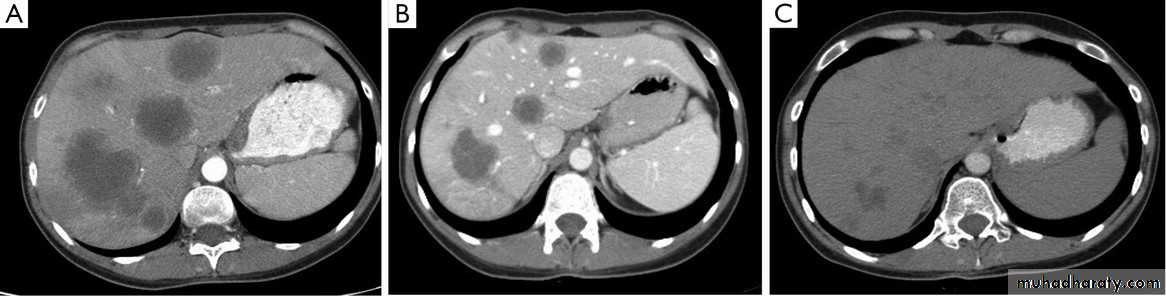

Secondary metastasis in the liver

Multiple rounded hypo density areas of different density , shape & different size .

Pattern of enhancement is either uniform , target or bulls eye pattern .

Hepato megaly .

Secondary metastasis within the liver